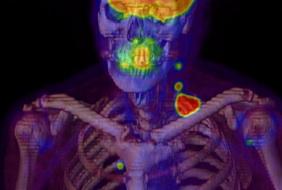

With today’s approval, Lymphoseek can now be used to guide testing of lymph nodes closest to a primary tumor for cancer, called a “sentinel” lymph node biopsy, in patients with cancer of the head and neck. This new indication will allow for the option of more limited lymph node surgery in patients with sentinel nodes negative for cancer.

“For some patients with head and neck cancer, removal and pathological examination of lymph nodes draining a primary tumor is an important diagnostic evaluation,” said Libero Marzella, M.D., Ph.D., director of the division of medical imaging products in the FDA’s Center for Drug Evaluation and Research. “To use Lymphoseek, doctors inject the drug into the tumor area and later, using a handheld radiation detector, find the sentinel lymph nodes that have taken up Lymphoseek’s radioactivity.”